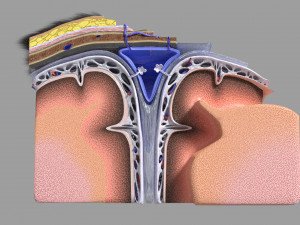

A blend model of brain along with its covering layers (meninges), skull bone and scalp labelled in detail and anatomically precise. The parts depicted are white, gray, pia, arachnoid, dura, bone, skin, fat, aponeurosis, periosteum, falx cerebri and more.

The material is high resolution image textures and normal maps based on non overlapping UVs. The texture and normal maps are packed with the blend file itself.